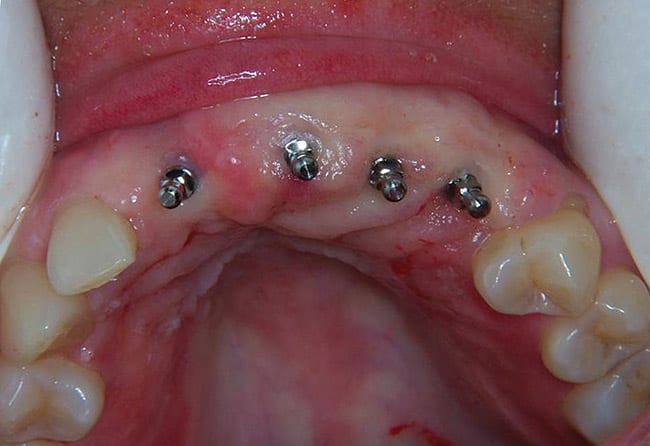

The mini dental implants used in this study were inserted such that the square neck portion of the implant was supragingival. O-ring housing abutments were then placed on the O-balls of the mini implants (Figure 8). With a pear-shaped laboratory bur, holes were placed in the patient’s denture at the previously marked locations. The denture was tried in the patient’s mouth for full seating. The holes in the denture were then filled with a housing resin or cold-cure acrylic. Before these materials set, the denture was placed on the O-ring housings and seated firmly. The patient was instructed to bite down for 3 to 5 minutes. The denture was then removed and the firmness of the housings was assessed. If housings were loose, the appropriate acrylic was applied. The denture with housings was then smoothed and adjusted to avoid patient discomfort and sore spot development (Figure 9). A postoperative radiograph can be seen in Figure 10.